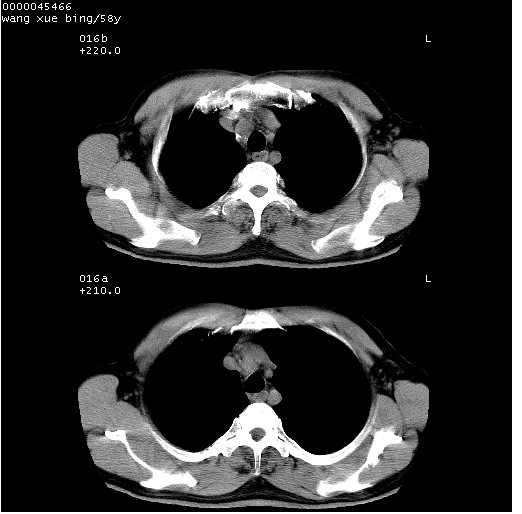

患者 男,58岁。咳嗽、咯血3月余。

胸部cr x线片提示:1)右下肺脓肿。2)右下肺周围型肺癌不排除。建议:行ct扫描检查。

胸部ct轴位平扫(层厚10mm,螺距1.5,重建间隔10mm),图像如下:

右肺下叶团块及不规则空洞,内壁不规则,外缘见粗长毛刺,临近胸膜明显增厚并与病灶关系密切。支持考虑:右肺肺脓肿!建议穿刺病理检查待除外周围型肺癌!

右肺下叶见不规则厚壁空洞,内壁不规则,外缘见粗长毛刺,临近胸膜明显增厚并与病灶关系密切。支持考虑:周围型肺癌!

右肺下叶周围型肺癌伴空洞形成!征象比较明显!分叶、毛刺、胸膜凹陷征、厚壁空洞,壁结节!

空洞壁厚,不规则,其内可见壁结节,周围可见毛刺及阻塞性炎变,多考虑癌性病变.